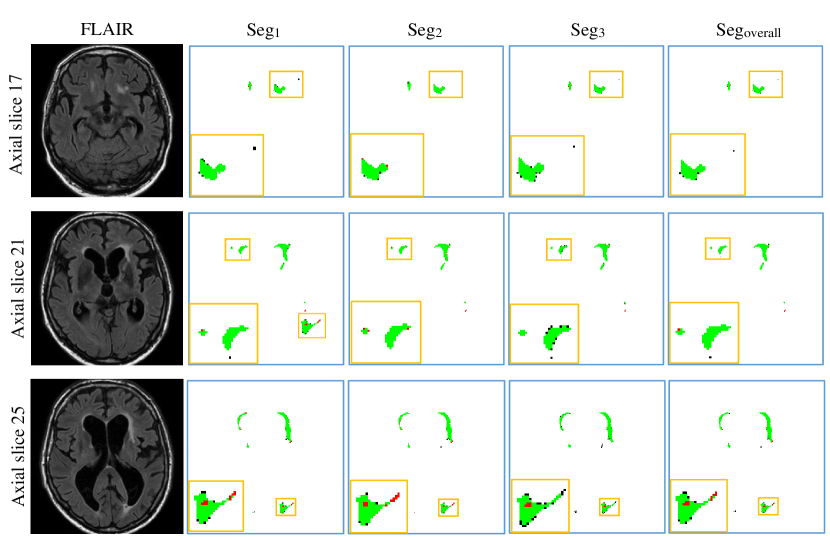

Figure 13 shows the curves of segmentation performance on five metrics w.r.t different ensemble size. It could be seen that (1) the ensemble with three or more models clearly outperformed the ensemble of only one model on all of the five metrics. The improvement of ensemble model with size over one with size is statistically significant on five metrics, all with small p-values; (2) when the size was further increased, performance tended to saturate and minor improvements in some of the measures came at the cost of small decreased in others. Figure 14 shows standard deviation of segmentation performance between five repeated trained models w.r.t different ensemble size. It could be observed that the variation of segmentation performance was reduced on the main evaluation metrics when the size of ensemble was increased. It demonstrated that the ensemble model can not only boost the segmentation performance but also guarantee a robust segmentation result. Figure 15 shows a case segmented by three individual models and their ensemble. We observed that three models trained with different weights initializations and shuffled data generated significantly different result on boundary and small lesions. And the model ensemble avoided the worst segmentation result.